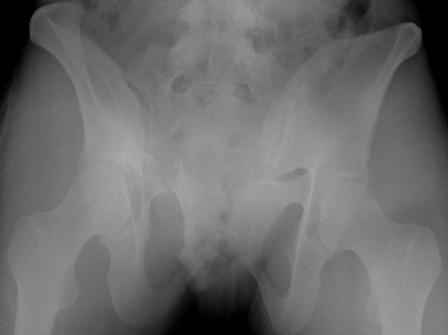

Ротационно-нестабильное повреждение.Наверняка есть перелом крестца слева.Нужно сделать проекцию хотя бы inlet.А в принципе можно скомбинировать, пластину на лоно + аппарат.

думаю, для начала необходимо определиться с типом перелома. Для этого, как минимум необходима проекция inlet, дальше часть вопросов может отпасть сама-собой.

Конечно важен механизм травмы, на первый взгляд возможно двустороннее повреждение задних отделов.